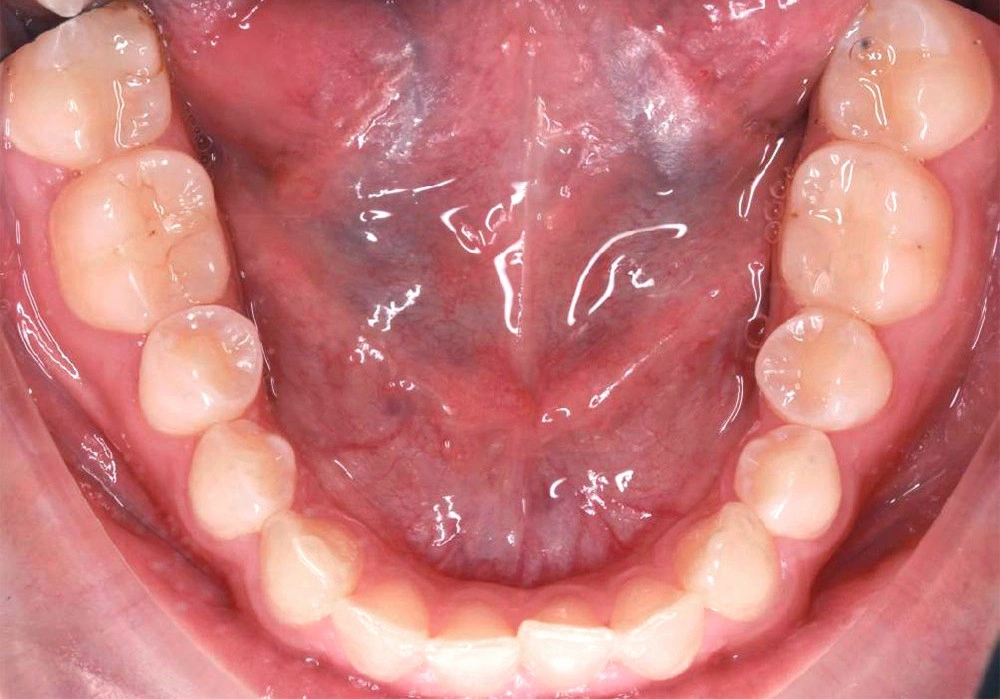

Глубокий прикус - Кейс 5

Эффективность устранения дефекта прикуса посредством элайнеров FlexiLigner.

Результаты лечения